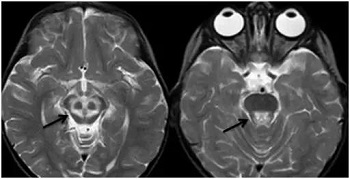

贾映海教授接着说,“小熊猫脸征”,中脑下部层面的双侧大脑脚、 上丘、 导水管、 导水管周围灰质核团、中央上核等构成了小熊猫脸的大体结构, 而双侧受累而呈长T2 信号的红核周围纤维束与短T2的中央被盖束勾勒出小熊猫的双眼。

贾映海教授说,熊猫征绝大多数为Wilson病(肝豆状核变性)的典型特征,也有个案报道见于Leigh病(亚急性坏死性脑脊髓病)。